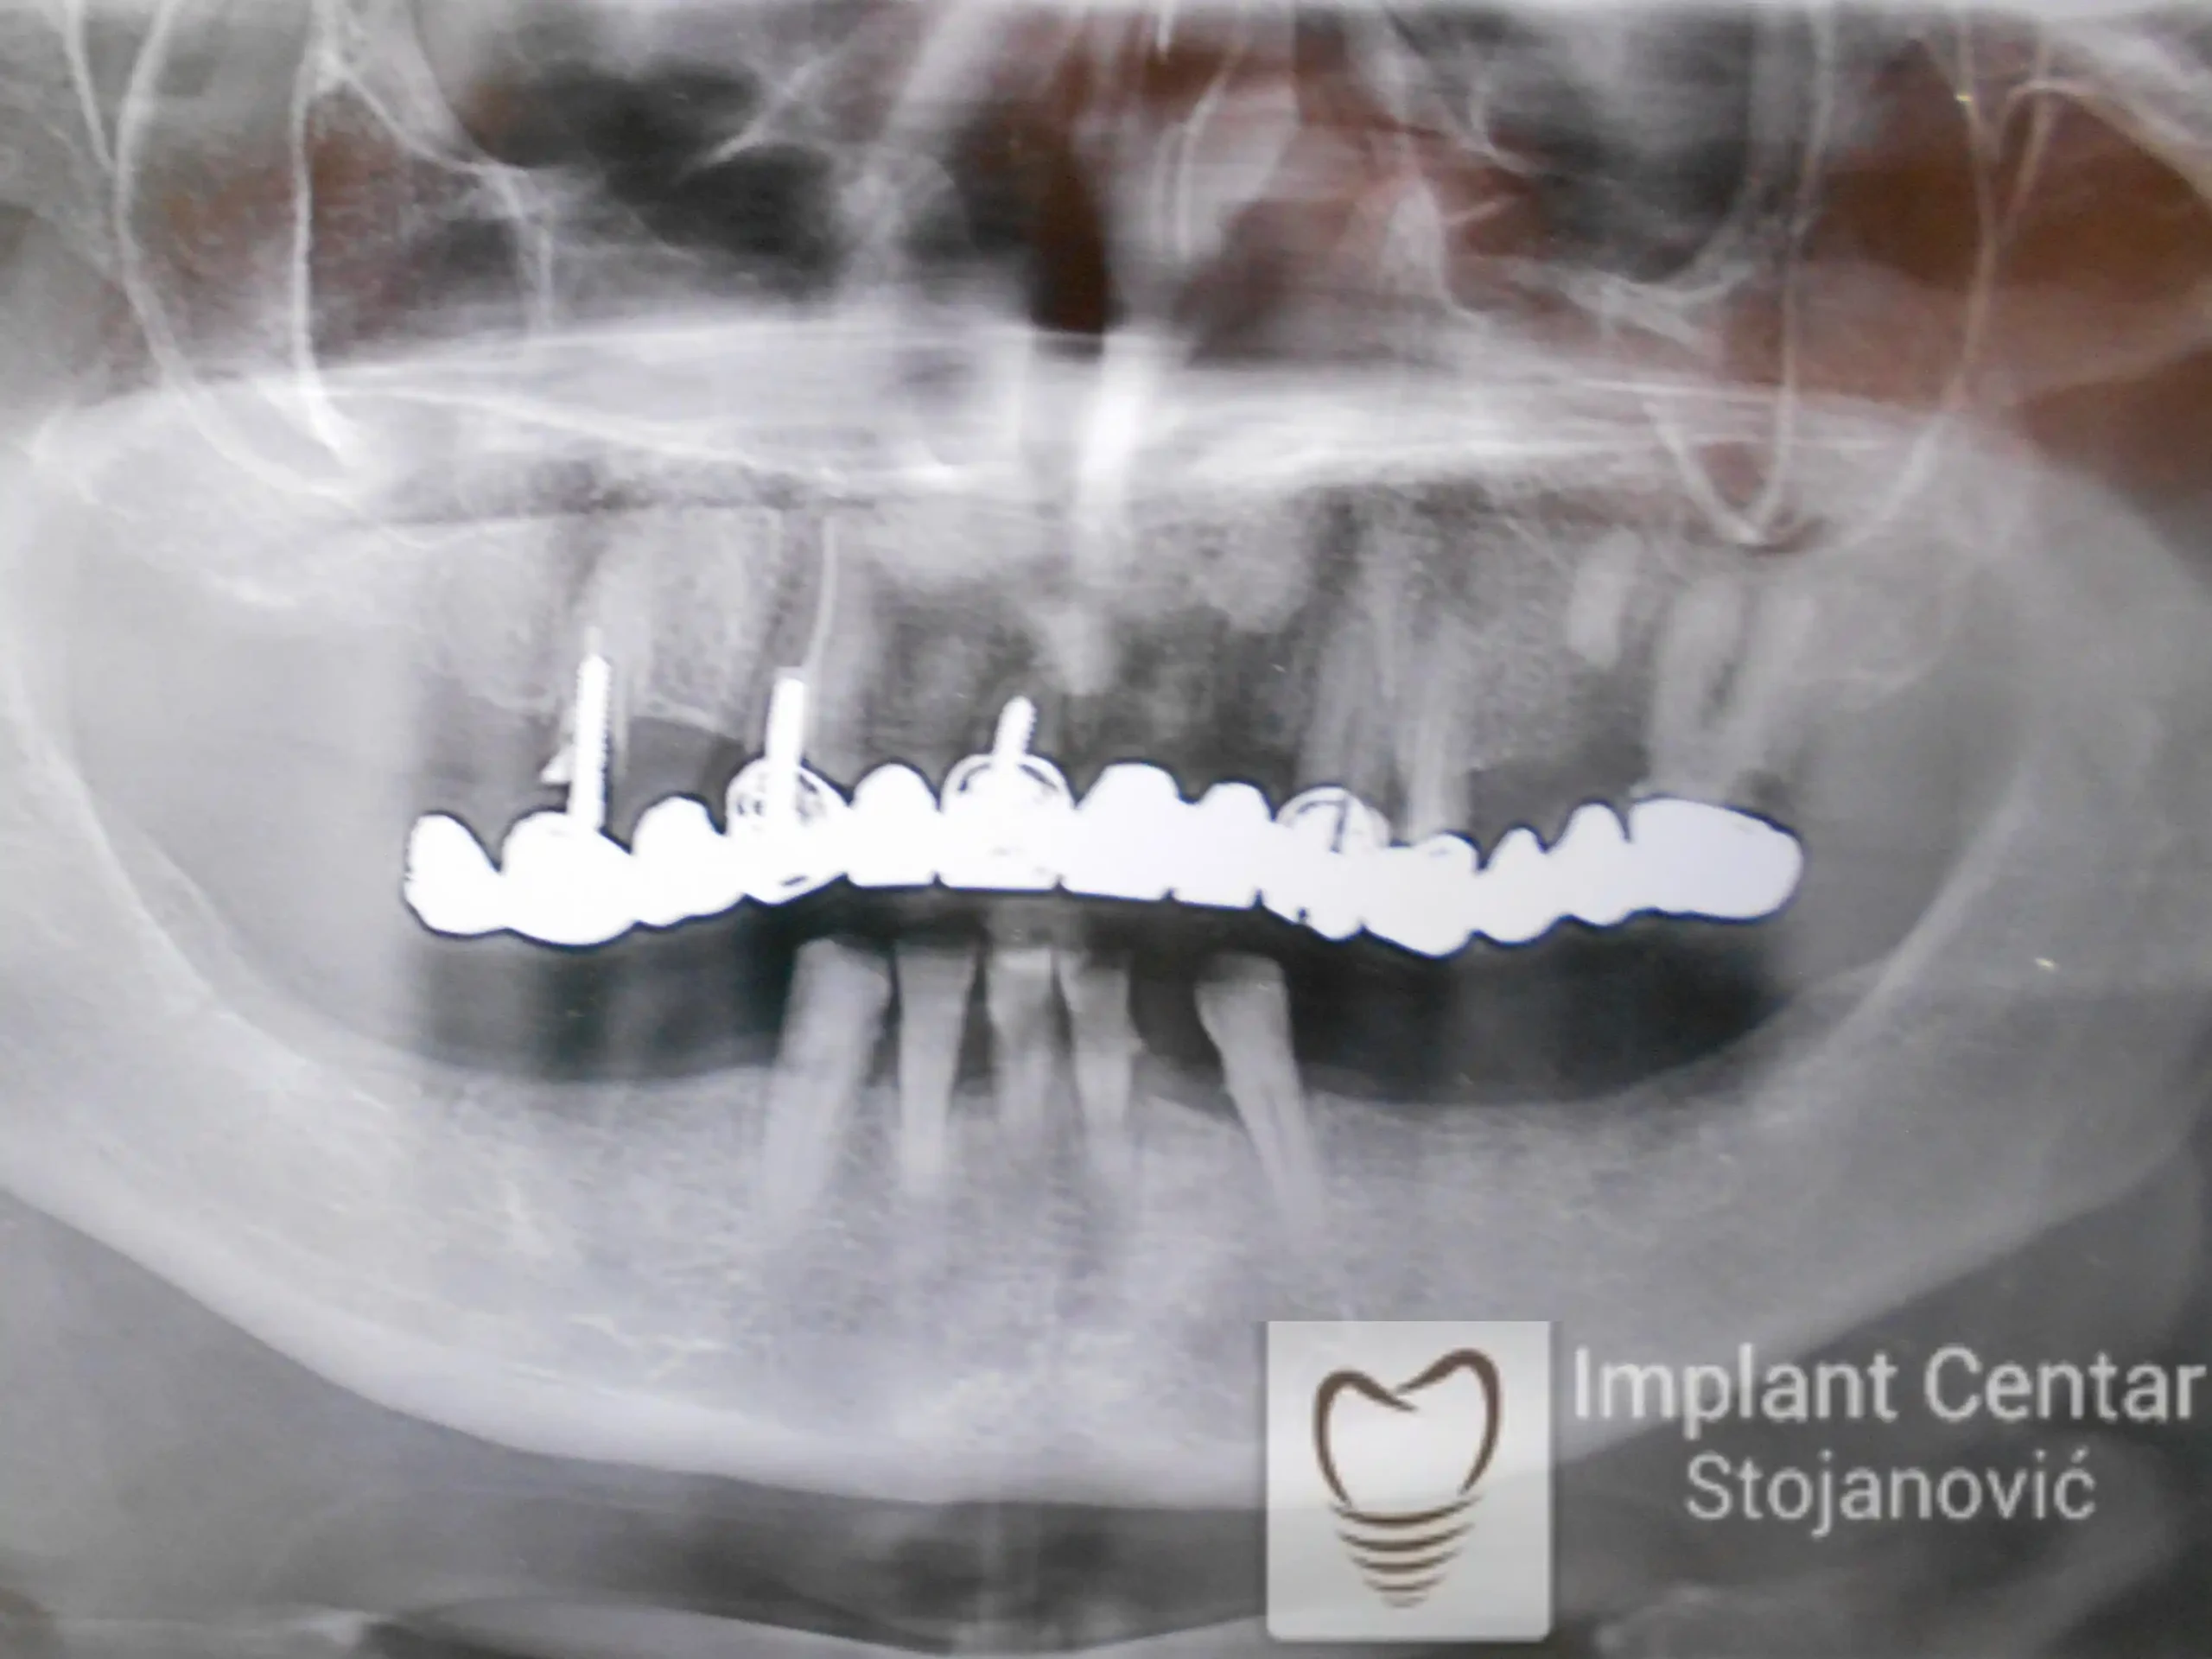

Zbog toga je plan terapije uključivao vađenje svih preostalih zuba i ugradnju implantata u gornjoj i donjoj vilici. U gornjoj vilici postavljena su i dva tuberopterigoidna implantata, kao zamena za sinus lift proceduru, što se može videti na ortopan snimku nurađenom odmah nakon ugradnje (slika 3).

Već tri dana nakon operacije, pacijent je zbrinut fiksnim privremenim zubima na implantatima, čime je odmah povraćena funkcija i estetika osmeha.